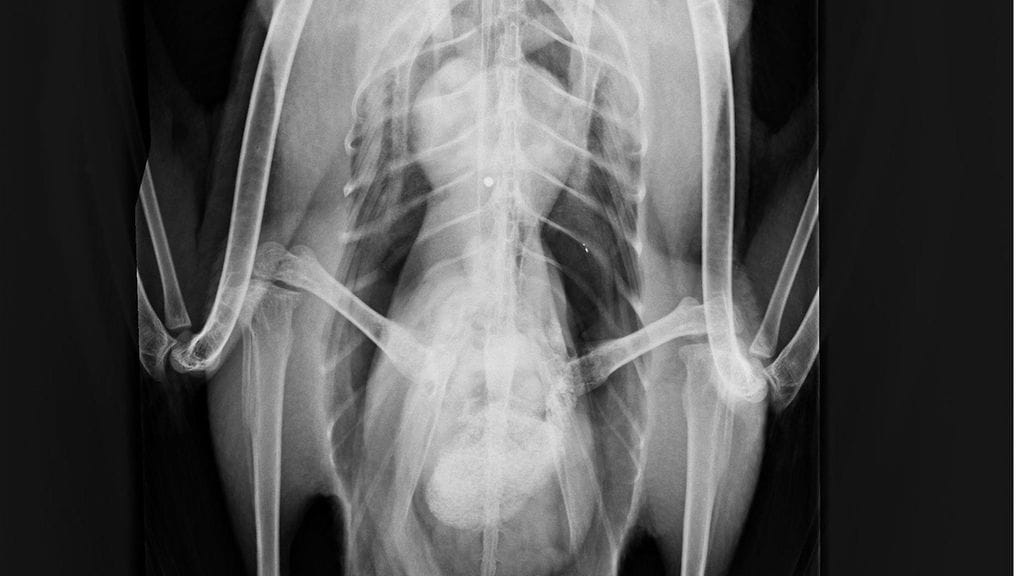

Kanadanhanhi nukutettiin tänään ja tutkittiin tarkemmin. Korkeasaaren mukaan röntgenkuvissa näkyi hauleja siivissä ja rintaontelossa.

– Kipulääkkeistä huolimatta siivet roikkuivat ilmeisesti hermovaurioiden tai hauleista ja vääntämisestä hajonneiden nivelsiteiden vuoksi.